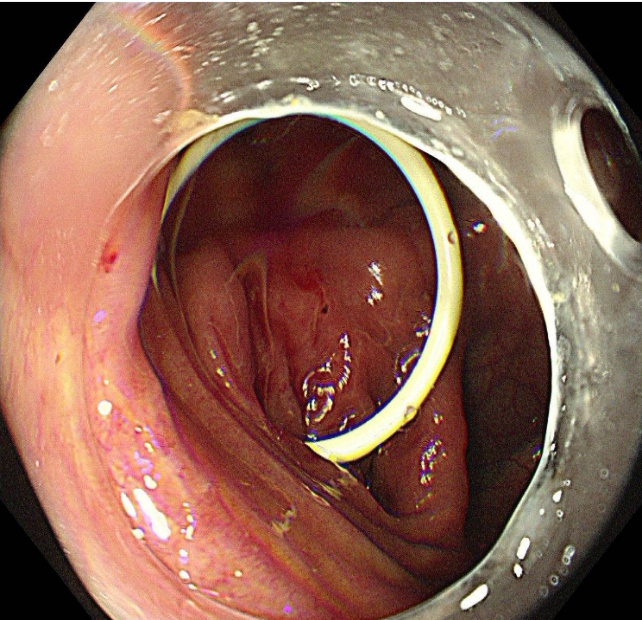

入院后完善腹CT检查精准锁定 “元凶”——阑尾粪石,这正是引发他反复腹痛的根源。考虑到小林的特殊身份,高考在即,时间紧迫,传统外科手术创伤大、恢复期长的弊端显而易见。消化内二科团队迅速组织病例讨论,结合患者年龄、备考需求及病情特点,决定采用肠镜下引入子镜直视下阑尾粪石取出术这一微创技术。该术式无需开刀,通过人体自然腔道即可完成操作,具有创伤小、恢复快、无疤痕等显著优势。

手术全程在高清内镜直视下进行,先将肠镜送至回盲部,定位阑尾开口后,小心翼翼地将子镜置入阑尾腔内。在高清内镜直视下,隐藏在阑尾里的粪石清晰可见。医护人员默契配合,利用专用取石器械,稳稳抓住粪石并缓缓取出。整个手术过程顺利,耗时短,创伤极小,患者全程不适。